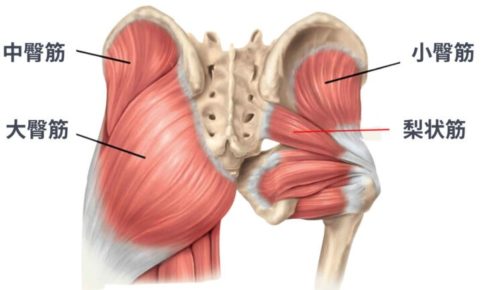

そんな声を聞くことがあります。膝は、太ももの前側(大腿四頭筋)や後ろ側(ハムストリングス)、お尻の筋肉(臀部筋群)など、周辺の筋肉がうまく働くことで安定しやすいと言われています。

特に大腿四頭筋は膝のお皿を支えているため、この部分が弱っていると膝への負担が増えやすいと説明されることがあります(引用元:knee-joint.net https://www.knee-joint.net/column/no28/)。